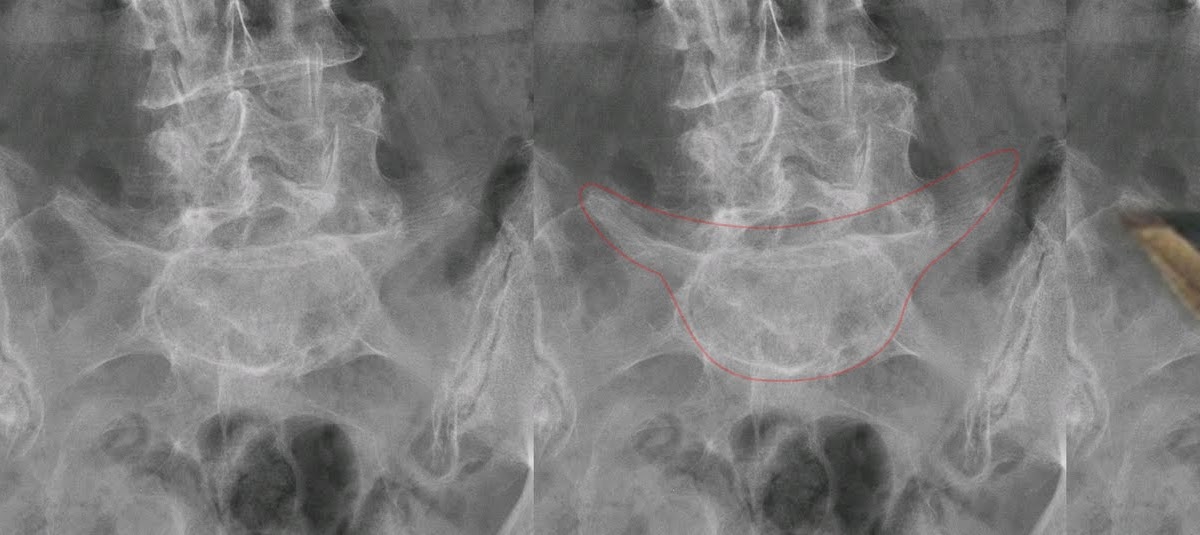

Radiograph of ls spine shows abnormal contour of the l5 vertebra. The recognition of these signs allows the radiologist to make a specific diagnosis or give a brief differential diagnosis. The inverted napoleon's hat sign.

The inverted napoleon hat sign refers to the appearance of the bicorne hat made famous by napoleon bonaparte.

Napoleon napoleonic red shako hat+cordon+white & red plume+free expedite shipp. The inverted napoleon's hat sign. It is seen when there is bilateral spondylolysis with marked anterolisthesis of l5 on s1 or marked exaggeration of the normal lordosis at the lumbosacral junction. Terms in this set (22) inverted napoleon hat sign= spondylolisthesis pronator fat pad sign= wrist fx (normal left, abnl right)